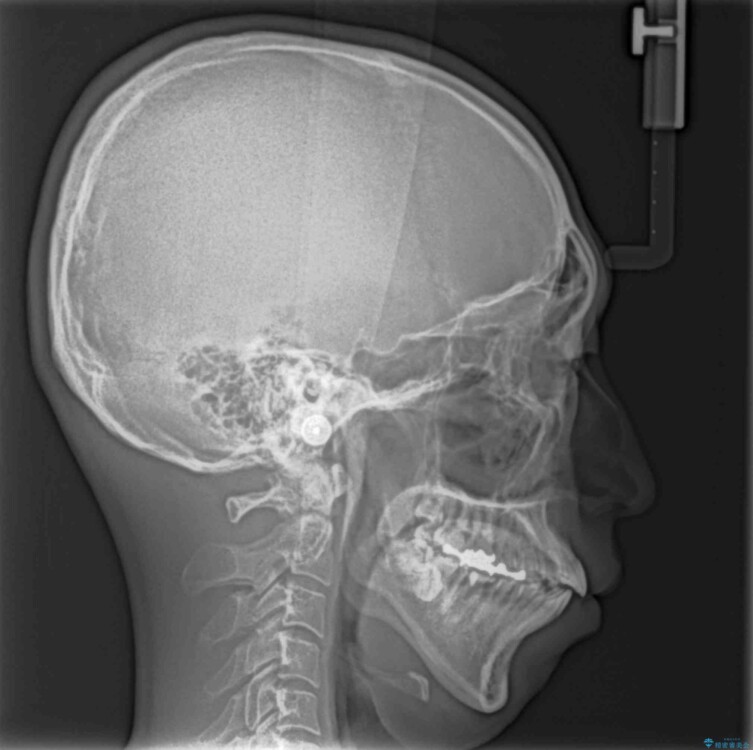

「横から見ると唇が前に出て見えるのが気になる…」 「マスクを外すのが恥ずかしい…」 そんな口元の突出感に悩まれてご来院された患者様。

精密検査の結果、上下左右の小臼歯4本を抜歯し、そのスペースに前歯を後方へ移動させる矯正治療をご提案しました。

治療前

• 口元の突出感を改善!目立ちにくいワイヤー矯正で自信を持てる自然な横顔に 治療前画像